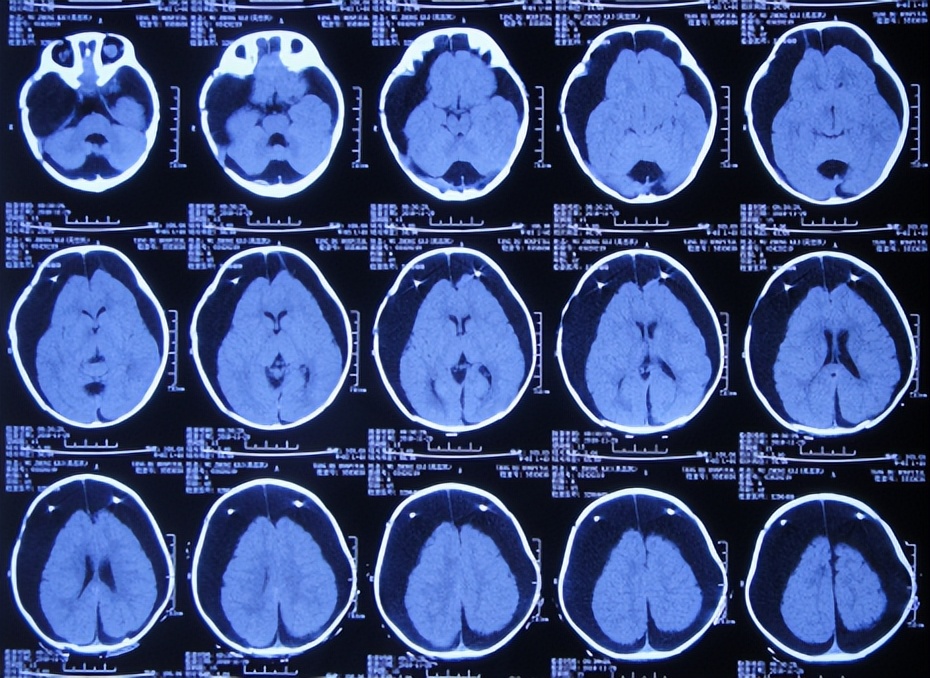

患儿2018年2月份,早产1月,剖宫产出生,出生后未见异常;患儿3个月大起,家属发现患儿头围较同龄幼儿大点,未给予重视;直到7个月大时,因发育迟缓自己不能坐,且头围进行性增大,于2018年9月11日,至当地第1家医院陕西省西康市白河县某医院,检查头颅CT发现双颞叶蛛网膜囊肿、脑积水( 图-1 )。

图-1: 2018年9月11日头颅CT